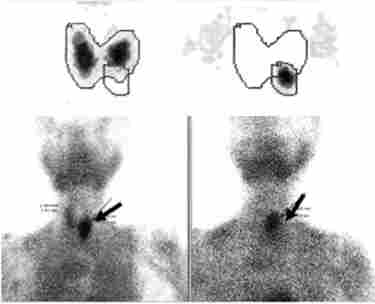

радіоізотопна сцинтиграфія гінерфункціонірующіх пухлин ОЩЖ реалізується за допомогою 99м7с або 201Т1 (Рис. 7.3). Цей метод дозволяє виявити збільшені ОЩЖ в 80-90% випадків (як при аденомі, карциномі, так і при гіперплазії ОЩЖ).

Результати сцинтиграфії з 7с хворих на первинний гіперпаратиреоз. Стрілкою вказані зони гіперфіксації радиофармпрепарата в області паратіреоаденоми

Мал. 73. Результати сцинтиграфії з 99м7с хворих на первинний гіперпаратиреоз. Стрілкою вказані зони гіперфіксації радиофармпрепарата в області паратіреоаденоми